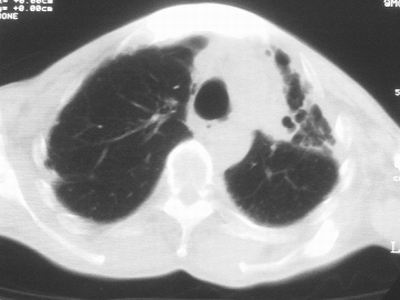

标题: CT11864:男,47岁,反复咳嗽、咯痰、咯血3年,请分析. [打印本页]

患者,男,47岁,反复咳嗽、咯痰、咯血3年,再发5天。痰培养未找到真菌、抗酸杆菌、癌细胞。

左肺上叶体积明显缩小,其内见多发透光区,纵隔向左侧移位,左肺下叶多发班片状病灶,边界模糊,1左肺上叶先天肺发育不全,2左肺下叶肺炎,

左肺上叶结核伴肺纤维化,纵隔移位,左肺下叶感染性病变,建议抗炎抗结核后复查,双肺气肿.

以下是引用xulianj在2008-2-25 21:01:00的发言:[br]左肺上叶结核伴肺纤维化有霉菌球形成,纵隔移位,左肺下叶感染性病变,建议抗炎抗结核后复查,双肺气肿.

考虑:左肺慢纤伴霉菌球形成、双肺全小叶型肺气肿。

1)考虑为:左肺上叶肺结核(空洞形成),伴左下肺感染;不排除霉菌感染可能。2)肺气肿。

左肺上叶结核伴肺纤维化空洞形成并左肺下叶感染,纵隔牵拉移位,建议作进一步检查排除左侧肺霉菌感染可能。